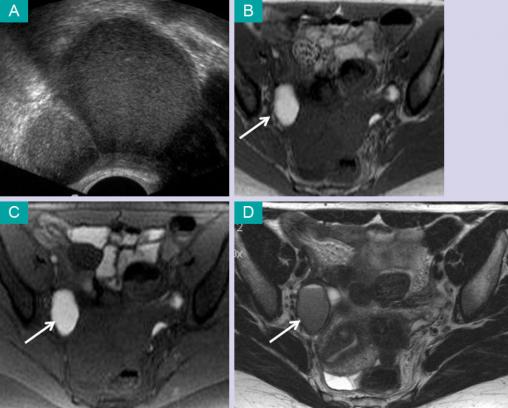

(A) Échographie pelvienne par voie endovaginale : kyste ovarien avec un fin piqueté échogène homogène. (B) Imagerie par résonance magnétique (IRM) en coupe axiale, en séquence pondérée T1 : kyste ovarien droit en hypersignal. (C) IRM en coupe axiale, en séquence pondérée T1 avec extinction du signal de la graisse : persistance de l'hypersignal. (D) IRM en coupe axiale, en séquence pondérée T2 : kyste ovarien avec un hyposignal (shading). Voir : Daraï É, Bazot M, Ballester M, Belghiti J. Endométriose. Rev Prat 2014;64:545-50.